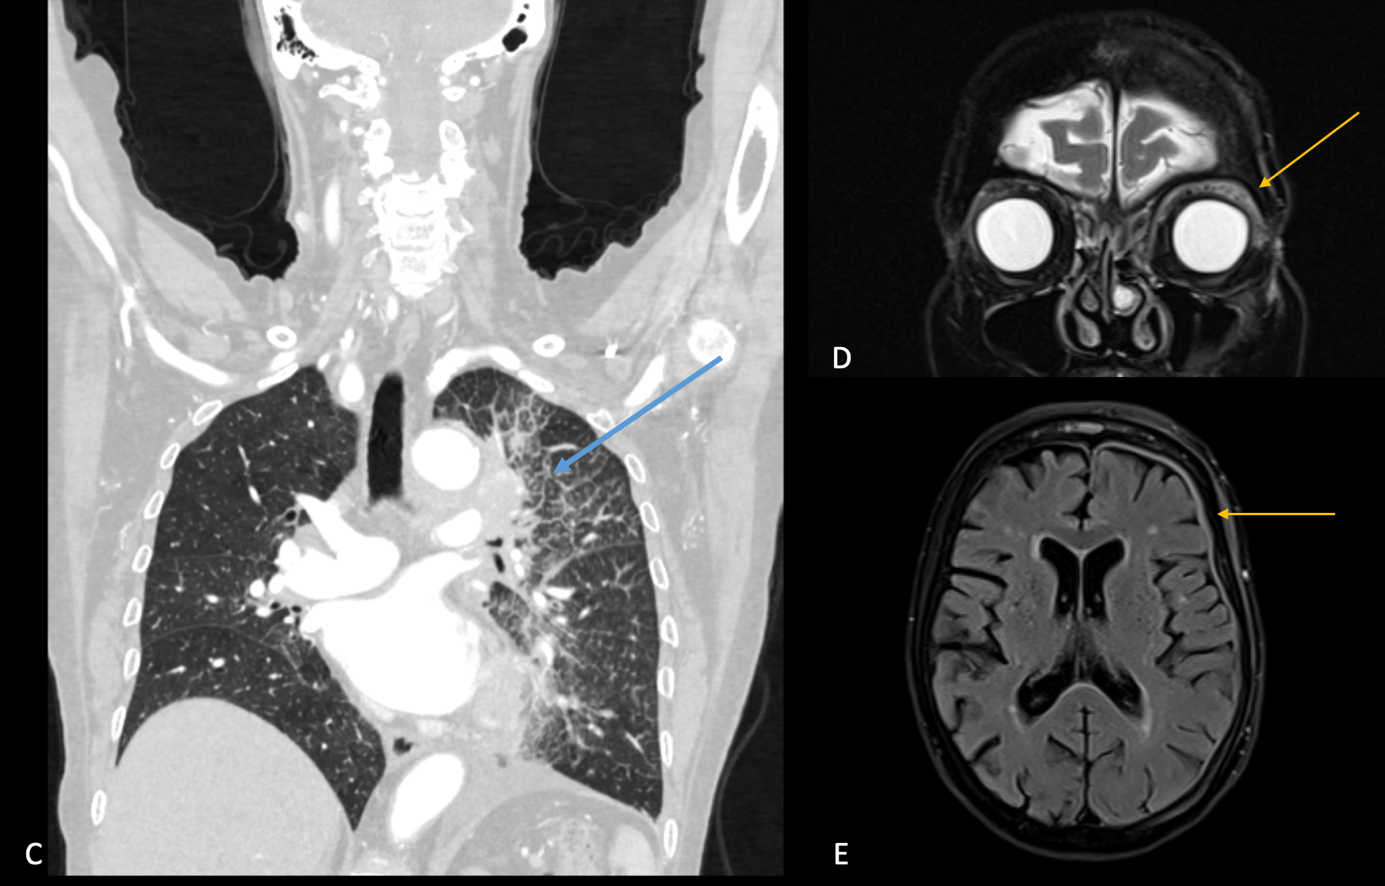

A, B, C. Axial und koronal rekonstruierte CT-Untersuchung in venöser Kontrastierung, hier zeigen sich zwei Rundherde im linken Oberlappen, Zeichnungsvermehrung mit retikulo-nodulärem Verteilungsmuster sowie ein moderater Pleuraerguss linksseitig.

D. T2 TSE koronal dark-fluid Sequenz, hier zeigt sich eine deutliche Inflammation des intrakonalen, retrobulbären Fettgewebes linksseitig.

E. Axiale T1 MPRAGE Post-KM, hier zeigt sich eine deutliche Verdickung und Enhancement der linksseitigen Pachymeningen.